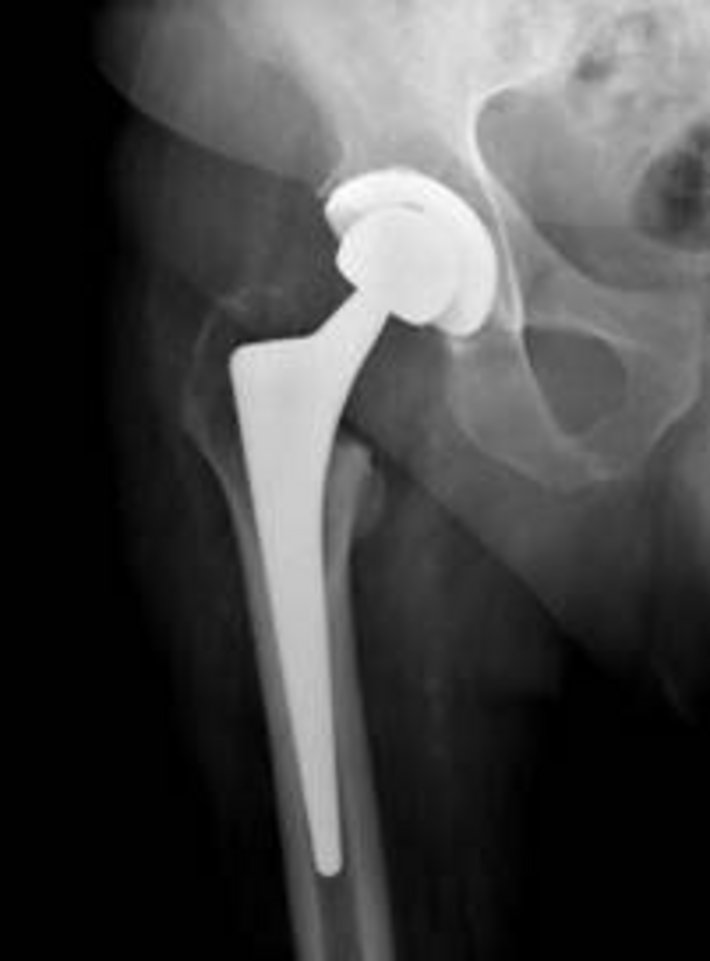

Es gibt verschiedene Modelle von künstlichen Hüftgelenken. Bei der Wahl der Prothese und ihrer Verankerung spielen unter anderem der Gesundheitszustand des Patienten, seine Knochenqualität und seine körperliche Aktivität eine Rolle. Ziel einer jeden Erstoperation ist es möglichst viel vom eigenen Knochen zu erhalten und die ursprüngliche Anatomie weitestgehend wiederherzustellen. Die Kunstgelenkmodelle, die dieser Aufgabe am besten gerecht werden, istdie Kurzschaftprothese. Diese können bei Patienten mit einem Lebensalter von unter circa 60 Jahren und guter Knochenqualität eingesetzt werden.

Das häufigste künstliche Hüftgelenk

Das künstliche Hüftgelenk, die sogenannte unzementierte Hüftendoprothese (Hüft-TEP), wird weltweit am häufigsten implantiert. Es besteht ein sehr langer Erfahrungszeitraum und man kann in den meisten Fällen eine hervorragende Funktion vorhersagen. Das Kunstgelenk wird in den Hüft- und Oberschenkelknochen passgenau eingebracht. Sowohl Gelenkspfanne als auch Hüftkopf werden dabei ersetzt. Sollte eine Knochenschwächung durch Osteoporose vorliegen, können die Gelenke mit Knochenzement sicher verankert werden (zementierte Hüftendoprothese).